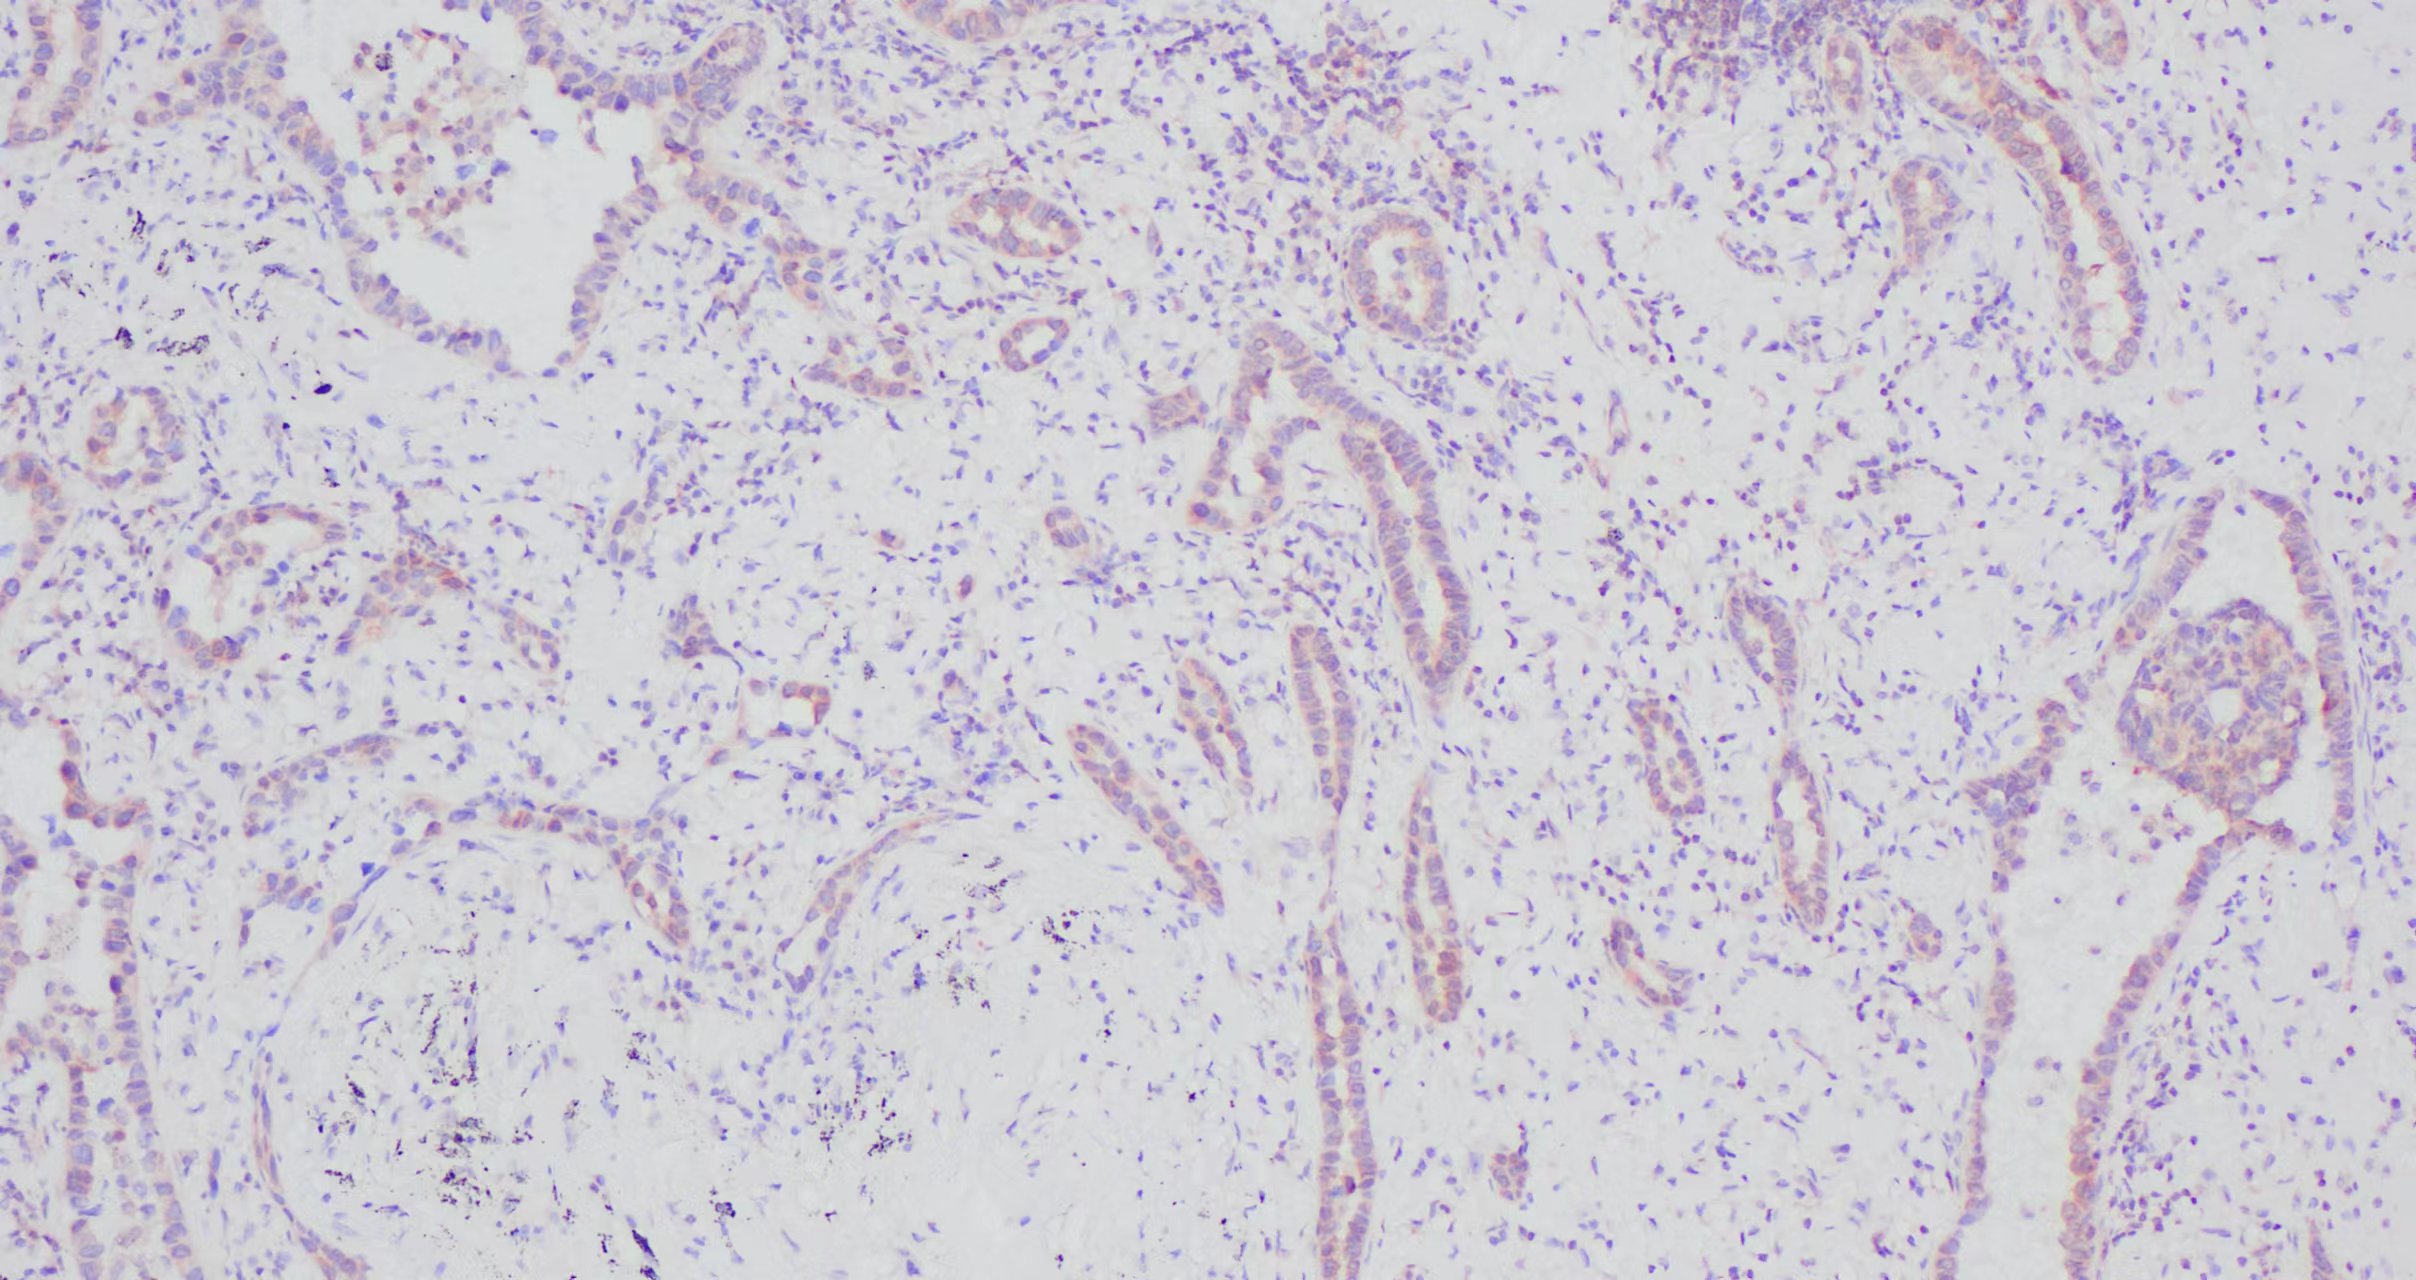

您的位置:首页 >> 产品介绍 >> IKBA 免疫组化

NFKB  扁桃体组�?.jpg